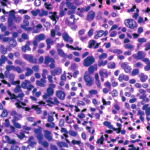

Pilomatrical carcinoma (matrical carcinoma) is a rare tumor found on the head and neck of older adults. Clinical appearances are generally not distinctive. Most cases probably develop de novo, but malignant transformation from a benign pilomatricoma has been reported. Histopathologic examination shows irregularly sized and variously shaped cutaneous/subcutaneous epithelial islands of basaloid (matrical and supramatrical) cells with conspicuous foci of shadow cells . The basaloid cells reveal nuclear atypia and mitoses, as well as areas of geographic necrosis.Pilomatrical carcinoma is primarily locally aggressive, but distant metastases, especially to lungs, bones, and lymphatics, have rarely been reported. Treatment of choice is surgical excision with adequate margins